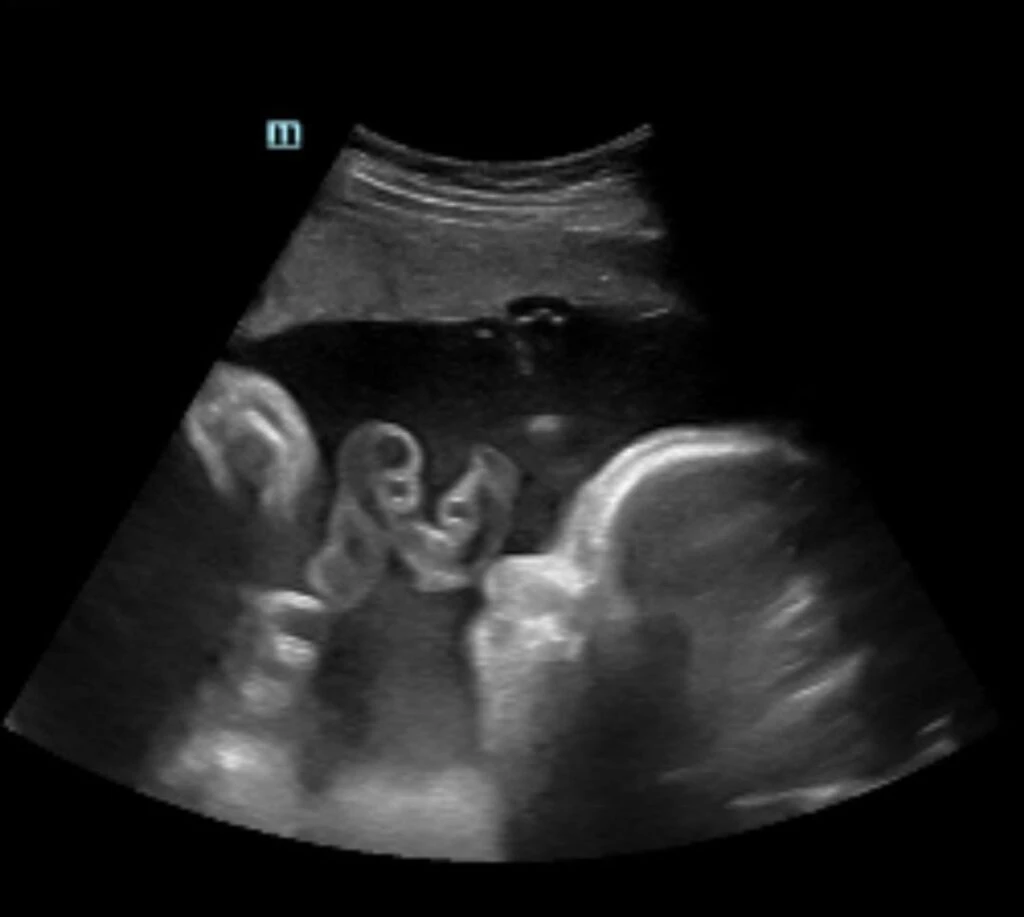

Pocos meses después, su médico le dio el aval para frenar con la terapia hormonal y en enero de 2024 le implantaron un ovocito e Ivana quedó embarazada. "Salvador nació el 20 de septiembre de 2024", afirmó con mucha emoción.